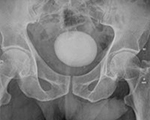

Any big bladder stone can be treated by per urethral cystoscopy fragmentation of stone by Laser Lithotripsy & removal. Average hospital stay 24 hrs & patient can resume duty next day. No need of blood transfusion. We have removed as large as 8 cm by 7 cm big stone endoscopically with holmium laser.